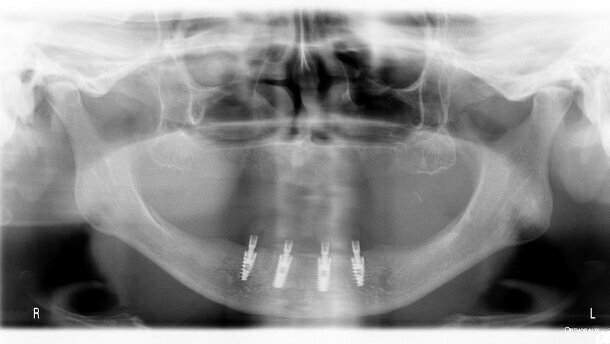

Po wykonaniu zabiegu chirurgicznego i uzyskaniu zgody pacjenta na przystąpienie do programu badań, ustalano indywidualny harmonogram wizyt kontrolnych. Każda wizyta obejmowała ocenę stanu higieny jamy ustnej, pomiar głębokości kieszonek dziąsłowych wokół wszczepów oraz wykonanie standardowego zdjęcia pantomograficznego. Ponadto, przeprowadzano standardowe zabiegi profilaktyczno-higienizacyjne. Wizyty kontrolne odbywały się co 4 tygodnie po implantacji przez 4 miesiące, następnie przez 4 lata co 6 miesięcy.

Stan higieny jamy ustnej oceniano wizualnie. Pomiarów głębokości kieszonek wokół wszczepów dokonywano przy użyciu standardowej sondy periodontologicznej. Także standardowo do oceny stanu tkanki kostnej wokół wszczepów wykonywano rtg pantomograficzne. Do usystematyzowania uzyskanych wyników zastosowano własną 4-stopniową skalę:

Uzyskane rezultaty przedstawiono w formie zbiorczej w tabelach 3-5 oraz na rycinie 1. Wybrane przypadki pokazano na rycinach 2-10. W całej badanej grupie odnotowano wystąpienie zapalnych zmian okołowszczepowych przy 60 implantach (9,8%). W 33 przypadkach zmiany o charakterze periimplantitis wystąpiły do 12 tygodni podczas gojenia zamkniętego. Pozostałe zmiany zapalne wystąpiły do 2 lat po obciążeniu funkcjonalnym i dotyczyły 27 wszczepów.